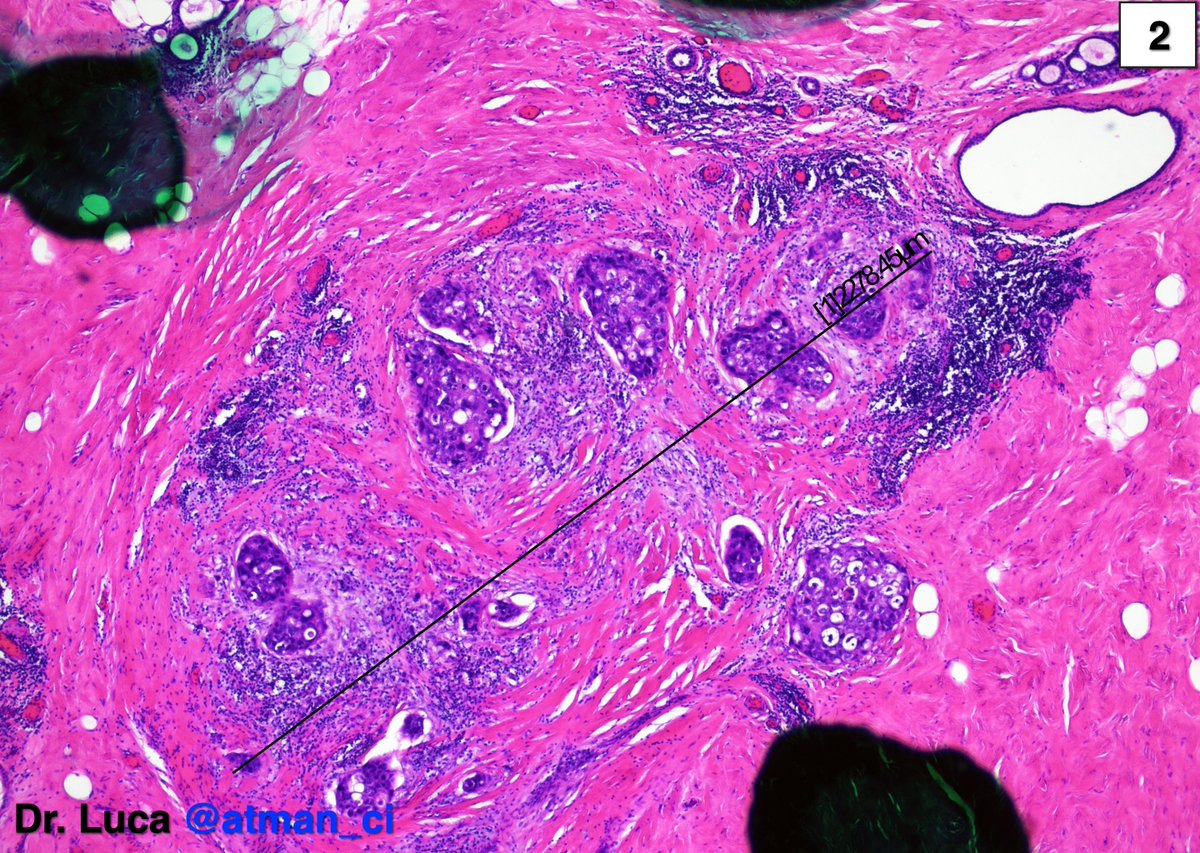

"Thanks all! MyoepIHC was + everywhere except in a µm focus (1), at the same time I resempled the specimen and I found a 2mm invasive focus (2-4). The SLN was N1(mi) @kriyer68 @LoboAnandi @QassidO @tlabiano @Jas_Bod @Ranges91 @migalf22 @bjbanji @pivonne10 #PathTwitter #BreastPath https://t.co/IIhjGU8Bcn"

(@atman_ci)